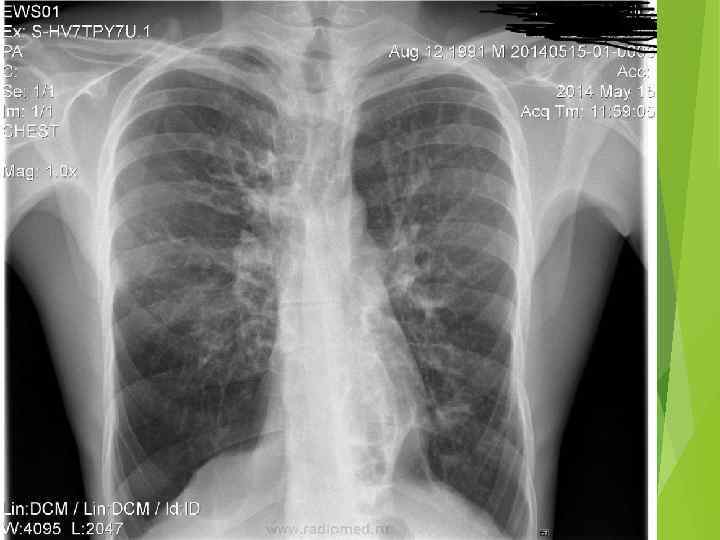

Скачать презентацию Лекция Семиотика заболеваний легких Рентгенограмма лёгких — Скачать презентацию Лекция Семиотика заболеваний легких Рентгенограмма лёгких —

лекция семиотика заболеваний легких.pptx